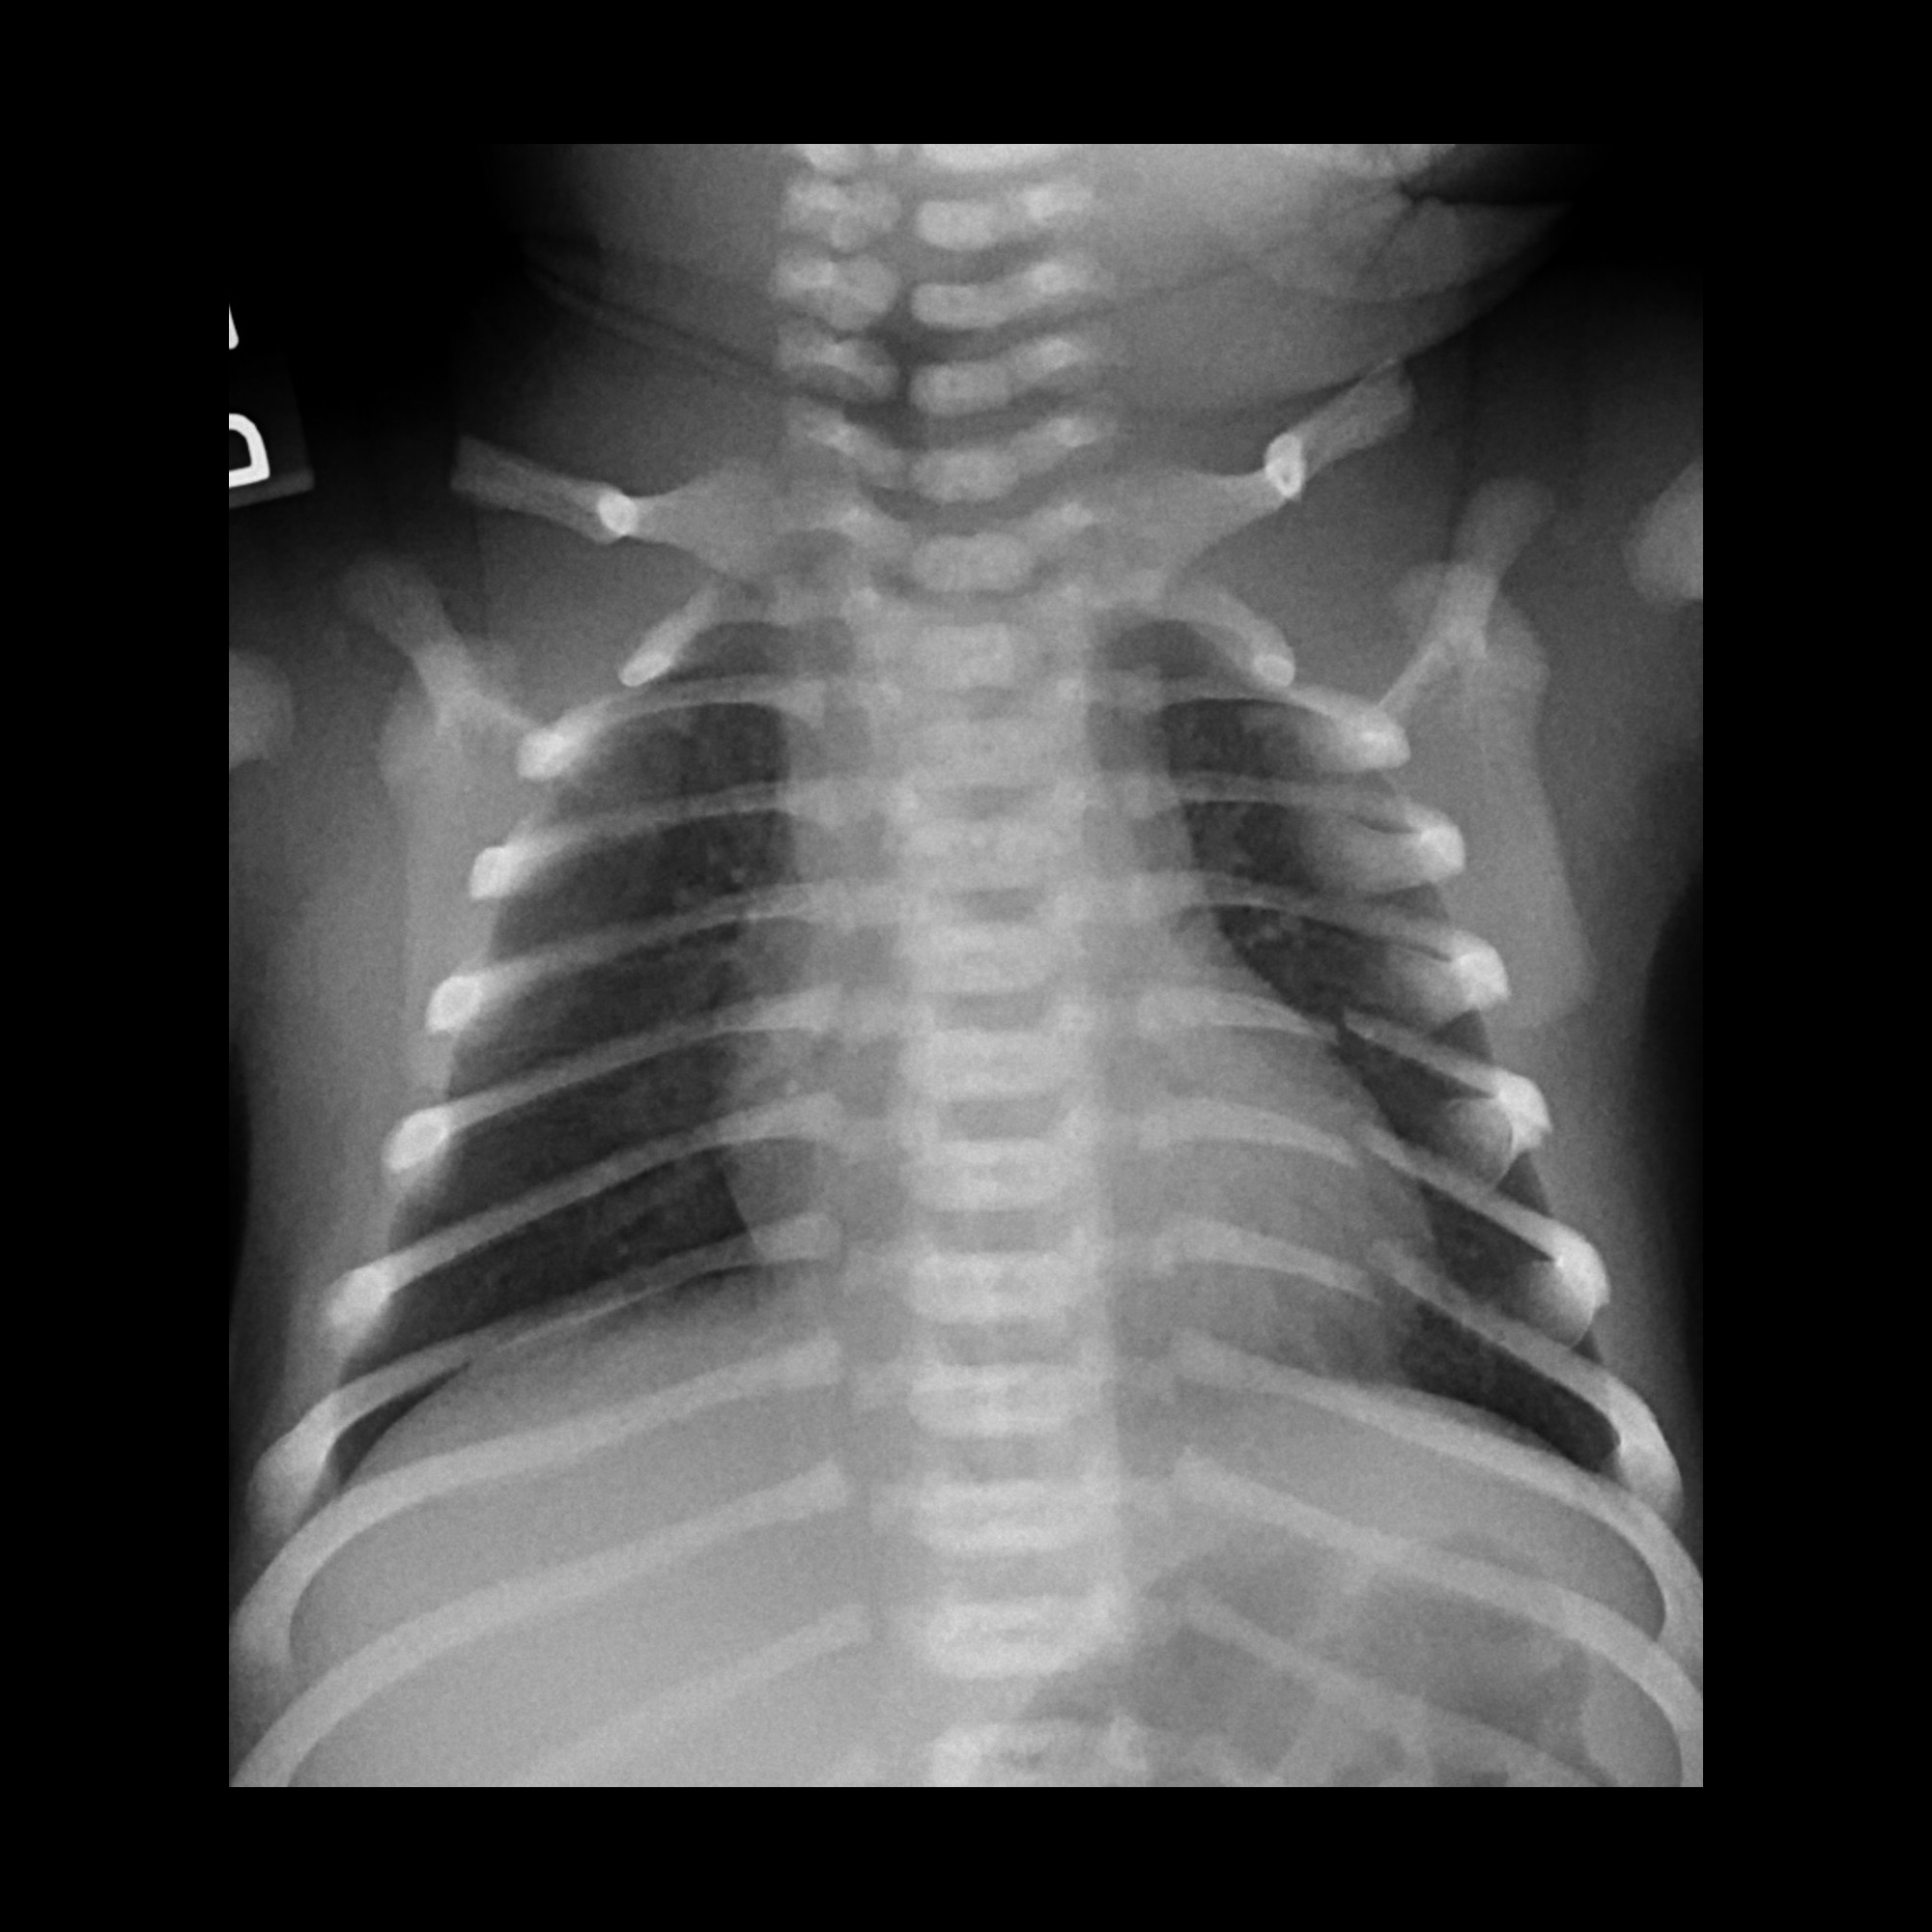

Shoulder dystocia is defined as a condition where one or both of the baby’s shoulders becomes caught on the mother’s pelvic bones, causing a necessity for certain maneuvers to be performed by the delivering provider in order to safely deliver the baby. These maneuvers are performed when gentle lateral traction on the baby’s head does not work in delivery. If a physician fails to perform the maneuvers properly or applies excessive force on the baby’s head or neck during delivery, the baby can suffer severe injuries including permanent nerve damage to the affected arm, hand and shoulder. This nerve damage is referred to as a brachial plexus injury. The mother may also experience injuries during these instances, including hemorrhages and tearing of the perineum. In particularly severe cases, either the mother or the child can die due to blood loss or oxygen deprivation.